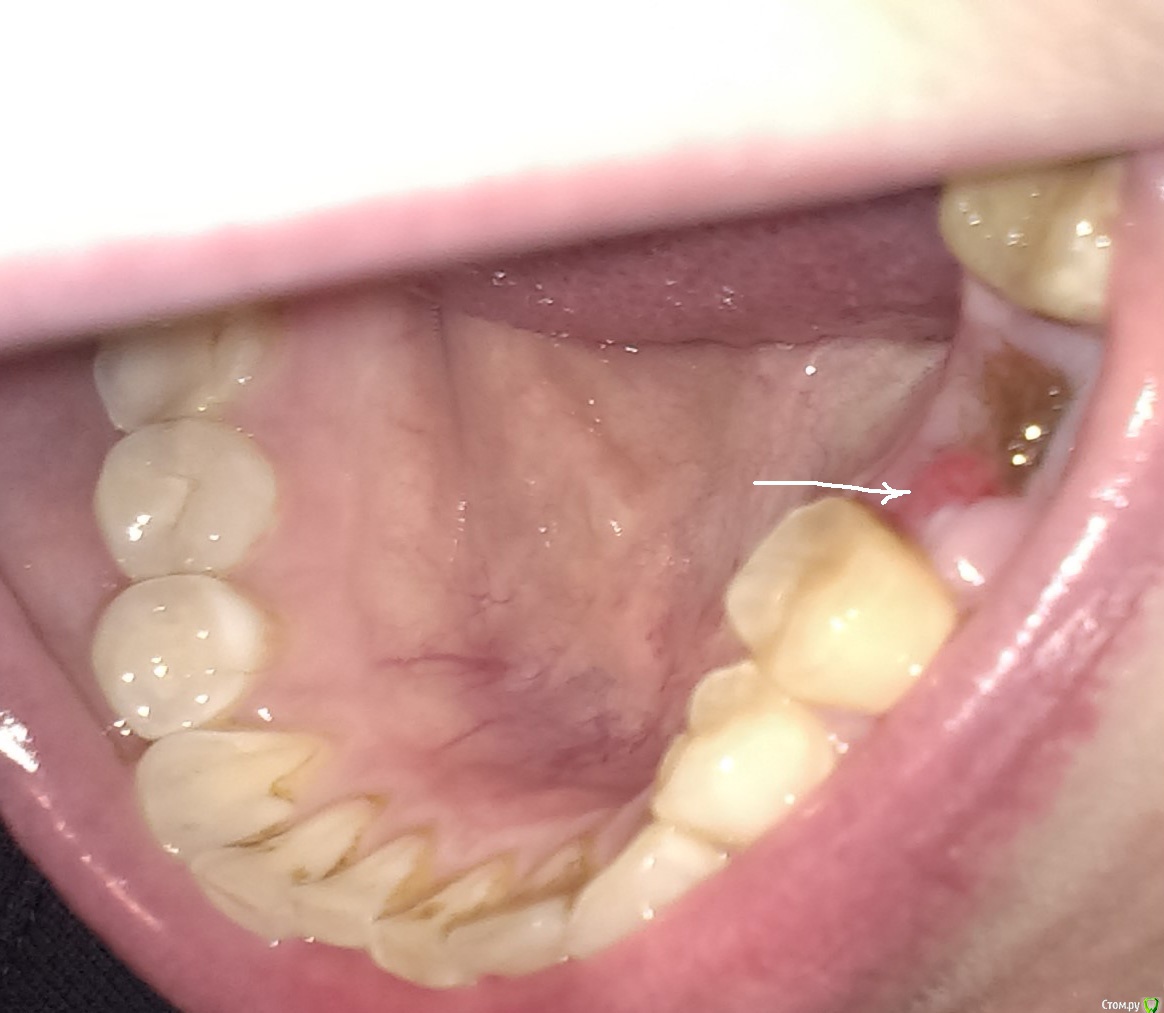

Scream Опубликовано 28 апреля, 2015 Автор Поделиться Опубликовано 28 апреля, 2015 Без осмотра сказать трудно. Положительная динамика если есть - то все будет ок.Положительная динамика началась вчера после метрогил дента (спасибо этому форуму - прочитала про данное средство и от безысходности начала накладывать на лунку со стороны покраснения). Боли уменьшились (но все еще есть, немного тянущие, отдающие в передние нижние зубы), спала без кетонала. Покраснение тоже стало поменьше. Подскажите, пожалуйста, означает ли это, что есть альвеолит? Лунка подзаживает, затягивается, никаких зияющих дыр в ней нет, до сих пор присутствует это коричневое волокно сверху, но с внутреннего края оно как бы отходит в сторону и видно что-то бело-серое под ним (сгусток?). Имеет ли смысл продолжать метрогил и ждать заживления или все-таки там может быть внутри воспаление и надо снова чистить? Четыре дня назад хирург сказал, что чистка сделает только хуже, дескать, не будем ворошить, но сегодня 8 дней с момента удаления, а картина вот такая непонятная... Прилагаю фото новое, может уважаемые доктора подскажут, есть ли смысл снова ехать к хирургу или продолжить метрогил?Благодарю всех за внимание к моей проблеме! Сегодня еще схожу на снимок. Ссылка на комментарий

rivezico Опубликовано 29 апреля, 2015 Поделиться Опубликовано 29 апреля, 2015 Если плохого запаха нет во рту, если сильно не болит и т.д. - то все будет норм. Метрогил можно до 7 дней наносить без проблем. Коричневое что сверху (ворсинки) -это альвожил. Его я убрал бы, если не уберете - то само постепенно уйдет. Убирать лучше у доктора, хотя у меня пациенты и сами убирали. Но мне трудно судить в Вашем случае-все индивидуально у всех, сами понимайте. 1 Ссылка на комментарий